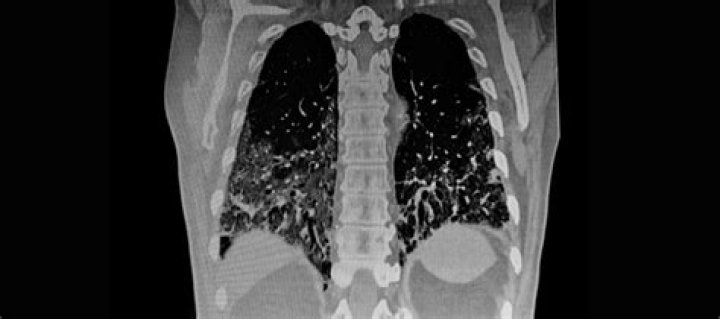

A spot on the lungs usually refers to a pulmonary nodule. This is a small, round growth on the lungs that shows up as a white spot on image scans. Typically, these nodules are smaller than three 3 centimeters (cm) in diameter. If your doctor sees a pulmonary nodule on a chest X-ray or CT scan, don’t panic.